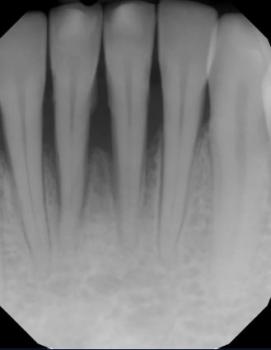

A dental examination and X-ray are required to confirm tooth and bone involvement.

Dental X-ray to check decay depth